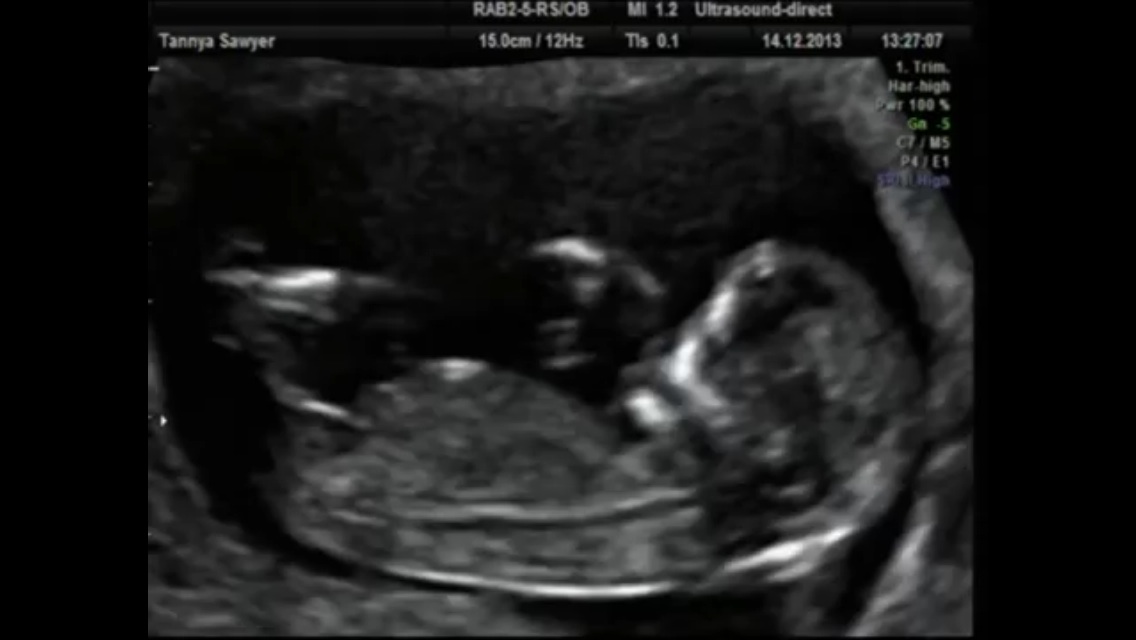

From this week onwards, your baby will grow rapidly and your doctor might suggest an ultrasound scan to check his progress . An ultrasound scan in the 13 th week can tell you a lot about your baby's health and is important . So read on to know why you should have an ultrasound scan at 13 weeks and how it is performed .

At 13 weeks pregnant, your baby is constantly growing . Now, he/she is more than 2 .8 in (7 cm) from the top of his/her head to the coccyx . Find out more about what is happening in week 13 of your pregnancy here .

This is the diameter between the two sides of the head and is measured after 13 weeks . It increases from about 2 .4 cm at 13 weeks to about 9 .5 cm at term . Different babies of the same weight can have different head size, therefore, dating in the later part of pregnancy is generally considered unreliable .